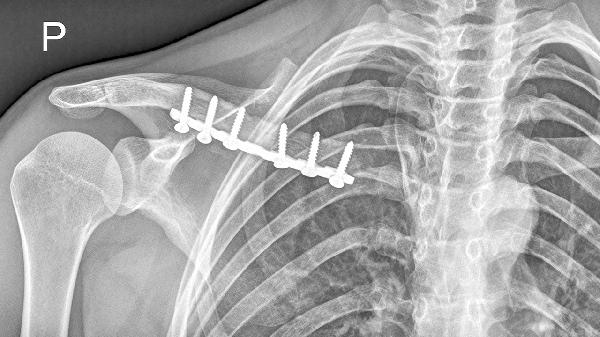

锁骨骨折通常采用八字绷带或锁骨带固定,严重移位需手术钢板内固定。钙片无法替代物理固定,但可为骨痂形成提供原料。固定期间需定期复查X线观察对位情况。

骨折后1-2周宜进食高蛋白流质食物如鱼汤、蒸蛋,避免辛辣刺激。3周后可增加乳制品、芝麻酱等富钙食物,配合日光浴促进维生素D合成。康复期避免提重物及剧烈运动,睡眠时保持患侧上肢垫高姿势。定期复查评估愈合进度,若8周后仍无骨痂形成需考虑调整治疗方案。补钙需在医生指导下进行,不可替代正规医疗措施。